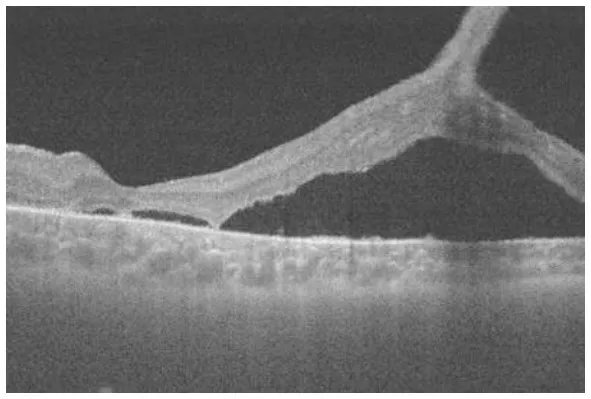

Fundus photograph (A), horizontal images of OCT at line B (B) and line D (D), magnified image of central section of OCT image B (C), and vertical OCT image at line V (V). OCT in the superior retina (at line D) showed no intraretinal split or cystoid changes (D, Grade 1 in Table 2), however OCT in the inferior retina (at line B) shows split/cystoid changes in GCL and INL (B,C,V) where no retinoschisis was observed in fundus photograph (A), i.e., “occult retinoschisis” (Grade 2 in Table 2).

Notably, in Patient 3-1, horizontal scanning inferior to the fovea (line B in Figure 3A) revealed minor splitting of the GCL and INL (Figures 3B,C), although ophthalmoscopy showed no peripheral retinoschisis (Figure 3A). However, horizontal OCT scanning superior to the fovea (line D in Figure 3A) showed no cystoid changes or retinal splitting (Figure 3D). An additional vertical OCT scan revealed cystoid changes/minor splitting in the INL continuously throughout the macula to the inferior retina. However, minor splitting of the GCL was observed in the peripheral retina but not in the posterior retina (Figure 3V).

Interestingly, ultra wide-field OCT revealed intraretinal retinoschisis in the inferior retina of Patient 3-1, where no retinoschisis was found by detailed fundus examination using an indirect ophthalmoscope or slit-lamp microscopy with a magnified fundus lens. Therefore, we propose the term “occult retinoschisis” to describe the optical coherent tomographic retinoschisis in Patient 3 (Figure 3B and Table 2).

Similar findings were reported by Gregori et al. (10) in 2013. They demonstrated minor splitting in the INL and GCL in the superior/inferior retina around the vascular arcades in a 13-year-old boy who presented shallow inferotemporal retinoschisis in the fundus. In our study, we successfully recorded OCT images outside of the vascular arcade using ultra wide-field OCT. Similar findings were also reported in the macular retinoschisis, in which lamellar retinoschisis was reported in the OCT images of a boy with XLRS who showed a clinically normal macula (18).

More than half a century ago, Yanoff et al. (19, 20) reported intraretinal retinoschisis in the inferior retina in an enucleated eye with XLRS, without bullous retinoschisis. They described the intraretinal retinoschisis as “early splitting within GCL or RNFL (19, 20).” Authors believe that the “occult retinoschisis” is the living image of the Yanoff-described “early splitting within GCL or RNFL.”

Both the Yanoff-described “early splitting within GCL or RNFL” and occult retinoschisis were found in the inferior retina (Figures 3B,V), while the peripheral retinoschisis was also frequently seen in the inferior retina in patients with XLRS (Figures 1A, 2A). These findings suggest that early splitting within the GCL or RNFL, or occult retinoschisis may be related to the development of peripheral retinoschisis. Therefore, patients with XLRS and occult retinoschisis (Grade 2) may have a higher risk of developing peripheral retinoschisis (Grade 3) than those without peripheral occult retinoschisis (Grade 1). However, whether occult retinoschisis can progress to peripheral retinoschisis, spontaneously resolve, or both, remains unclear, as only Patient 3 showed occult retinoschisis, and no ultra wide-field OCT-follow up was presented in this study.